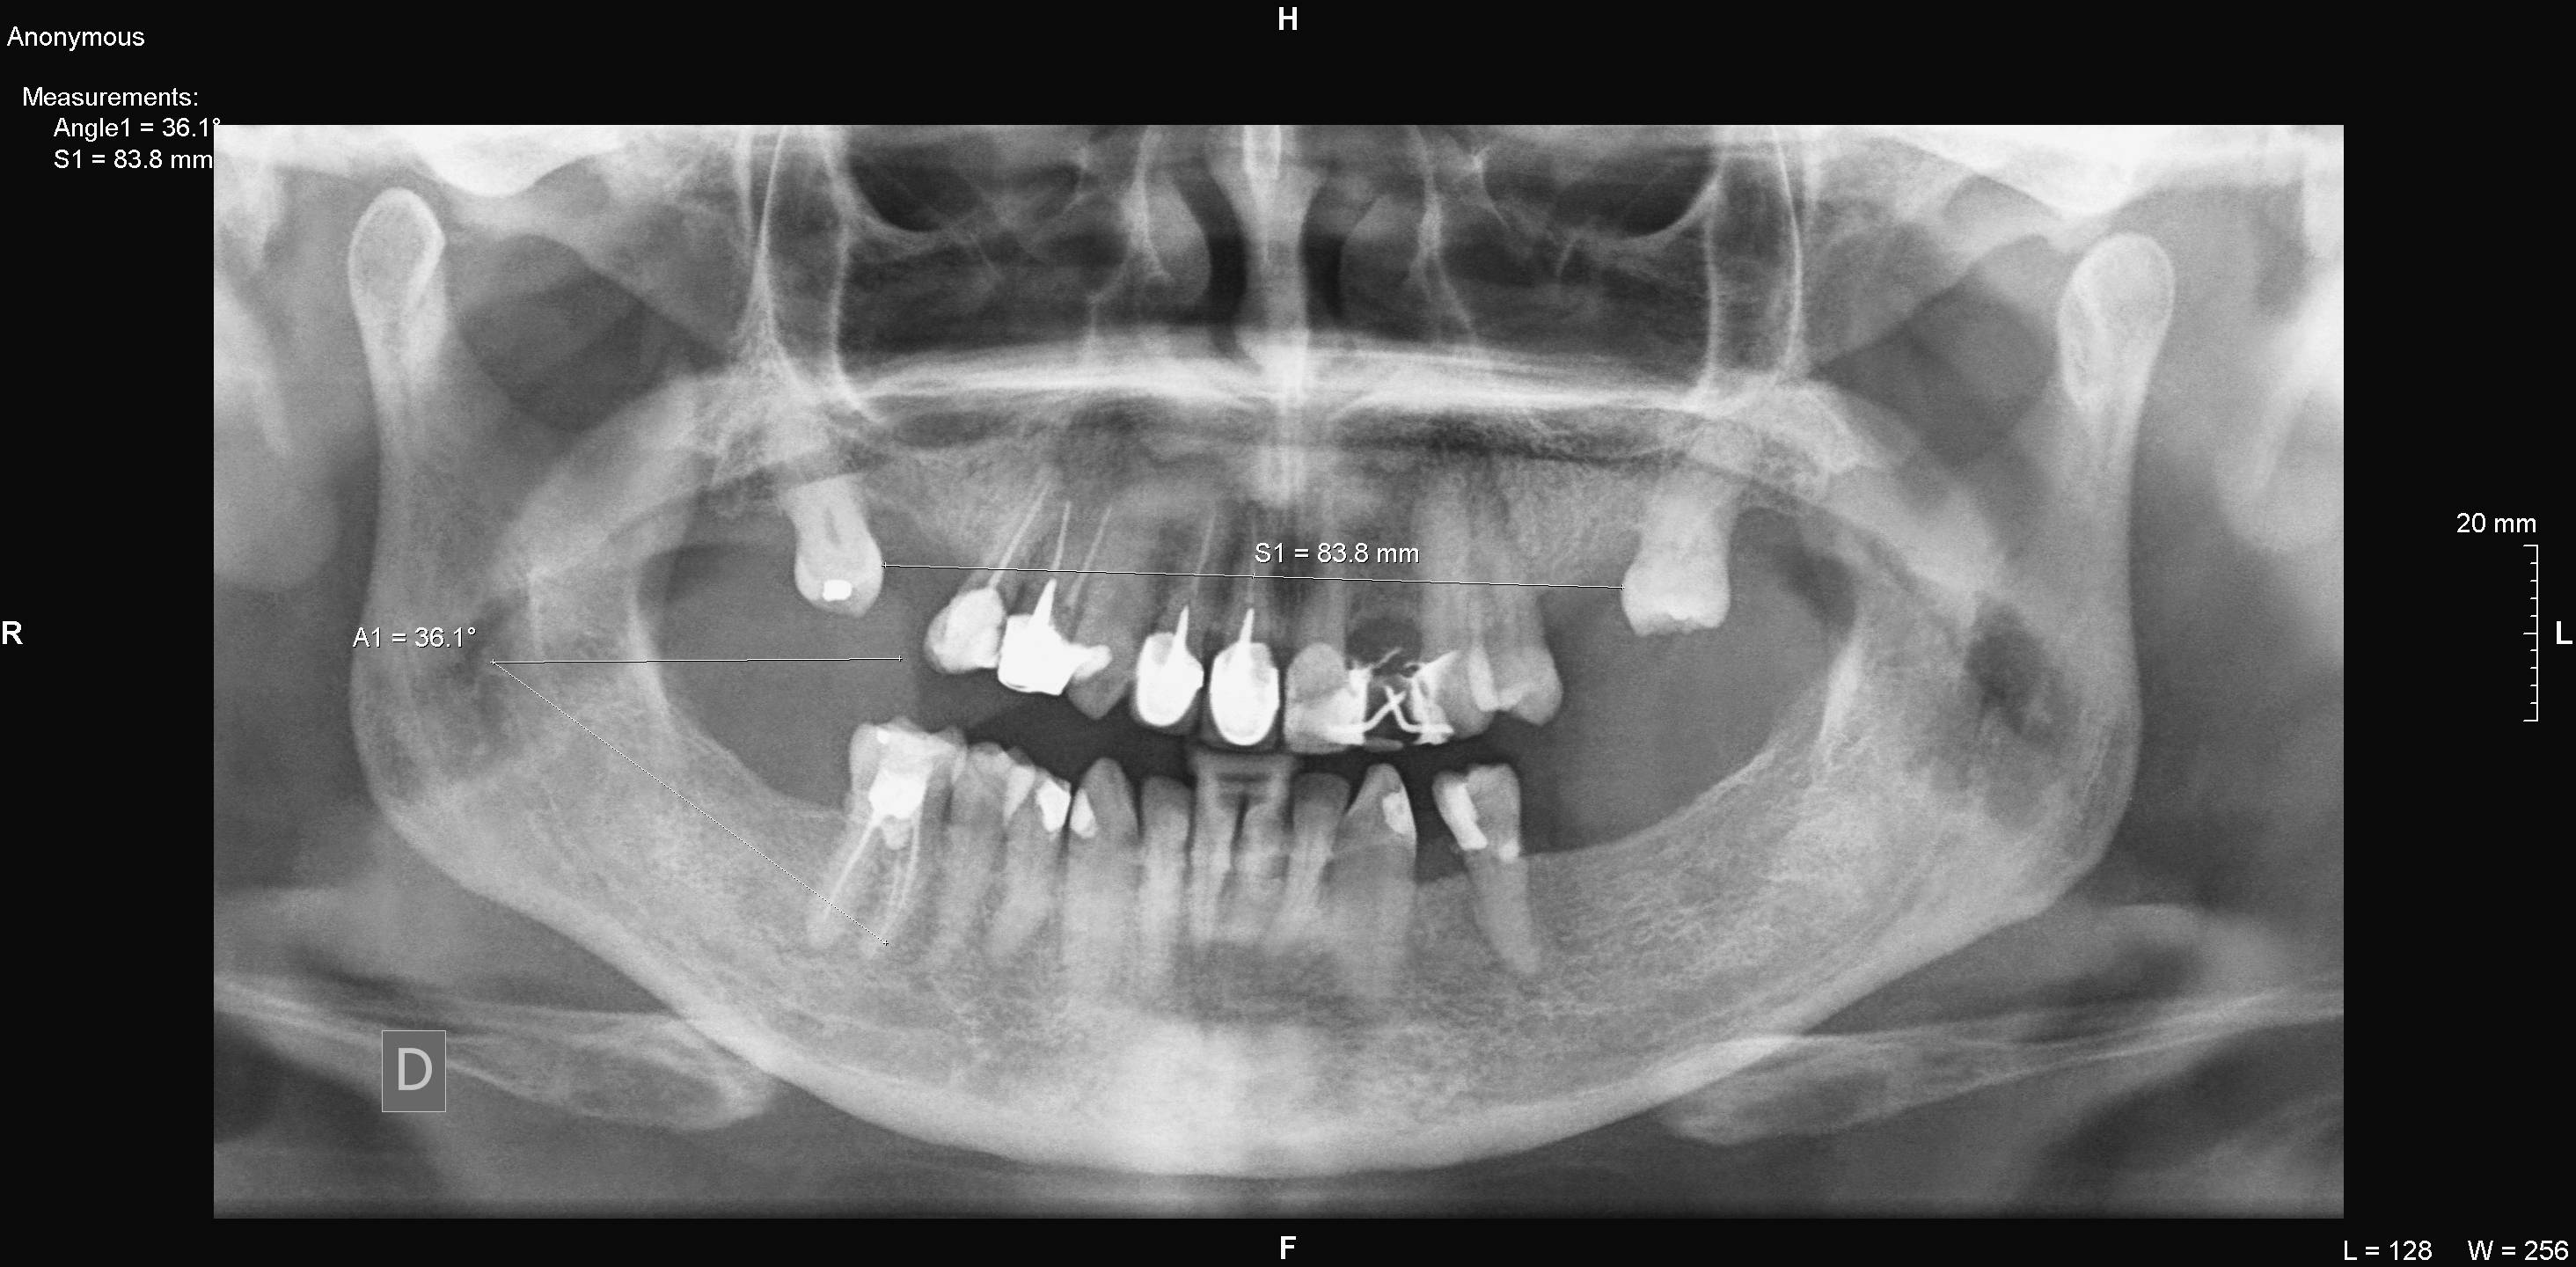

Algunos ejemplos de imágenes digitales

Pulse en las imágenes para ver la ampliación

Se agregó en rojo una medición hecha con la herramienta de medida

14lado